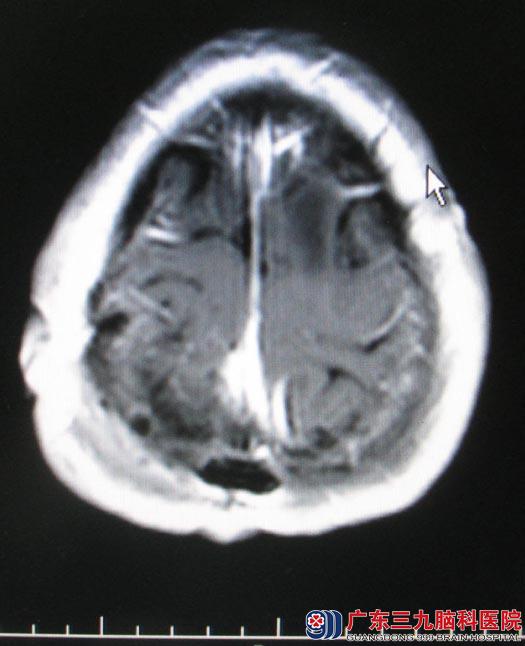

经过慎重的术前准备,5月26日由鲁明主任主刀,先作右侧顶部马蹄形切口,切开硬膜后见右侧顶部大脑镰窦旁灰白色肿瘤组织,肿瘤基底向矢状窦内生长,予显微镜下切开部分矢状窦,取瘤钳取出静脉窦内肿瘤,修补静脉窦,完全切除肿瘤。再作左额部弧形切口,在导航引导下皮层造瘘,见皮层下灰红色肿瘤组织,肿瘤呈鱼肉状,血供丰富,予显微镜下小心分离并切除。术后吴女士肢体运动等功能均恢复良好。病理回报:右侧顶部过渡型脑膜瘤(WHO1级);左侧额叶胶质肉瘤(WHOⅣ级)。